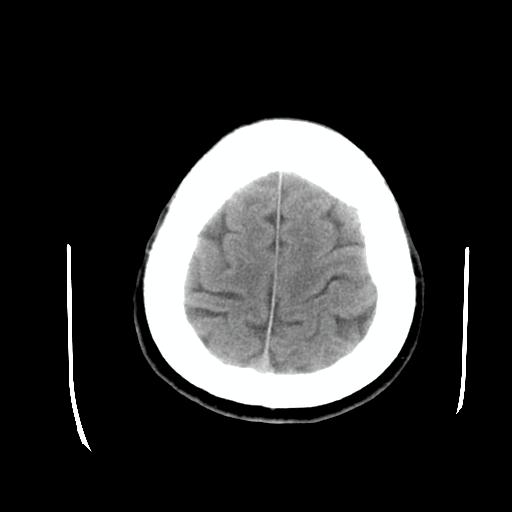

比较下

脉络丛囊肿属神经上皮性囊肿.好发于双侧脉络膜球,通常于影像检查或活检时偶然发现.患者无症状,病灶较小,双侧对称性,脑室膨胀轻.多数病灶在信号上与室管膜囊肿有所不同.在dwi上呈部分高信号,t2 flair上呈不均匀高信号.增强后呈结节状或环形增强

脉络丛囊肿属神经上皮性囊肿.好发于双侧脉络膜球,通常于影像检查或活检时偶然发现.患者无症状,病灶较小,双侧对称性,脑室膨胀轻.多数病灶在信号上与室管膜囊肿有所不同.在dwi上呈部分高信号,t2 flair上呈不均匀高信号.增强后呈结节状或环形增强!支持!